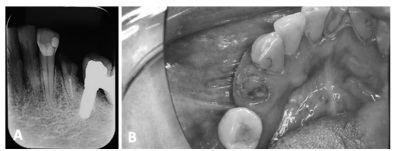

Com base no caso clínico descrito, julgue o item subsecutivo.

A remoção da raiz residual, demonstrando uma apreensão satisfatória, poderia ocorrer por meio da técnica primeira com uso de fórceps 151, cujo formato permite a mobilização radicular.